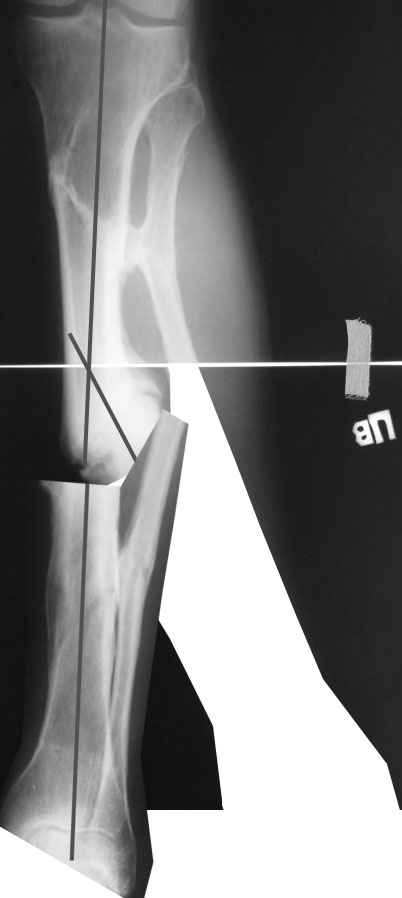

Одномоментно такой угол устранить трудно, сильно натянутся ткани по наружной поверхности голени. Может и стопа повиснуть. А что по второй проекции?

Мы бы сделали после остеотомии малоберцовой и аппаратной коррекции. Большеберцовую можно исправить за счет растяжения пседартроза. Можно и сделать поперечную остеотомию чуть дистальнее несращения, в этом случае будет удобный вход в периферический отломок. А зону несращения пройти разверткой просто по прямой. Схема в приложении.

Александр Николаевич, вечер добрый! Извиняюсь за отсутствие второй прекции. там тоже ещё та деформация! Дозировано исправлять - не уверен что идиально получится выставить по оси дистальный отломок, а смещение даже на кортикал, не влияющие на консолидацию в аппарате, при формировании канала и введении стержня в условиях вальгуса и рекурвации, ну не знаю. Второй вариант, о котором и вы говорите, думаю более предпочтителен. А если делать остеотомию дистальнее ложняка, то что помешает одномоментно откоррегировать? Парез и при аппаратной коррекции с той же долей вероятности может быть.

Да все реально. Чтобы эти трудности уменьшить, лучше углы и ширину устранить с небольшой гиперкоррекцией, а главое - создать запас по длине.

Ткани сильно натянутся. И закрыто вывести дистальный отломок под гвоздь будет проблематично, даже если дистрактор наложить. Можно попытаться одномоментно сопоставить, но без фанатизма. Ели что не устраняется сразу, аппаратом за несколько дней дозированно уже

дотягиваем.